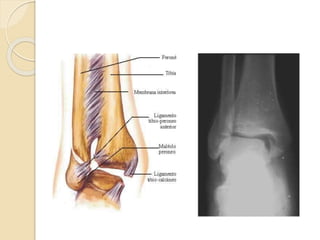

VISTA ANTERIOR DE LA

ARTICULACIÓN.

 La estabilidad de la articulación viene dada

por la configuración de la mortaja y por los

ligamentos, de los que hay tres grupos:

A- ligamentos de la sindesmosis:

constituidos por el ligamento tibioperoneo

anterior, el ligamento tibioperoneo

posterior, el ligamento transverso inferior y

el ligamento interóseo.

B- ligamentos del complejo lateral externo.

C- ligamento lateral interno es el deltoideo

con sus dos fascículos superficial y

profundo.